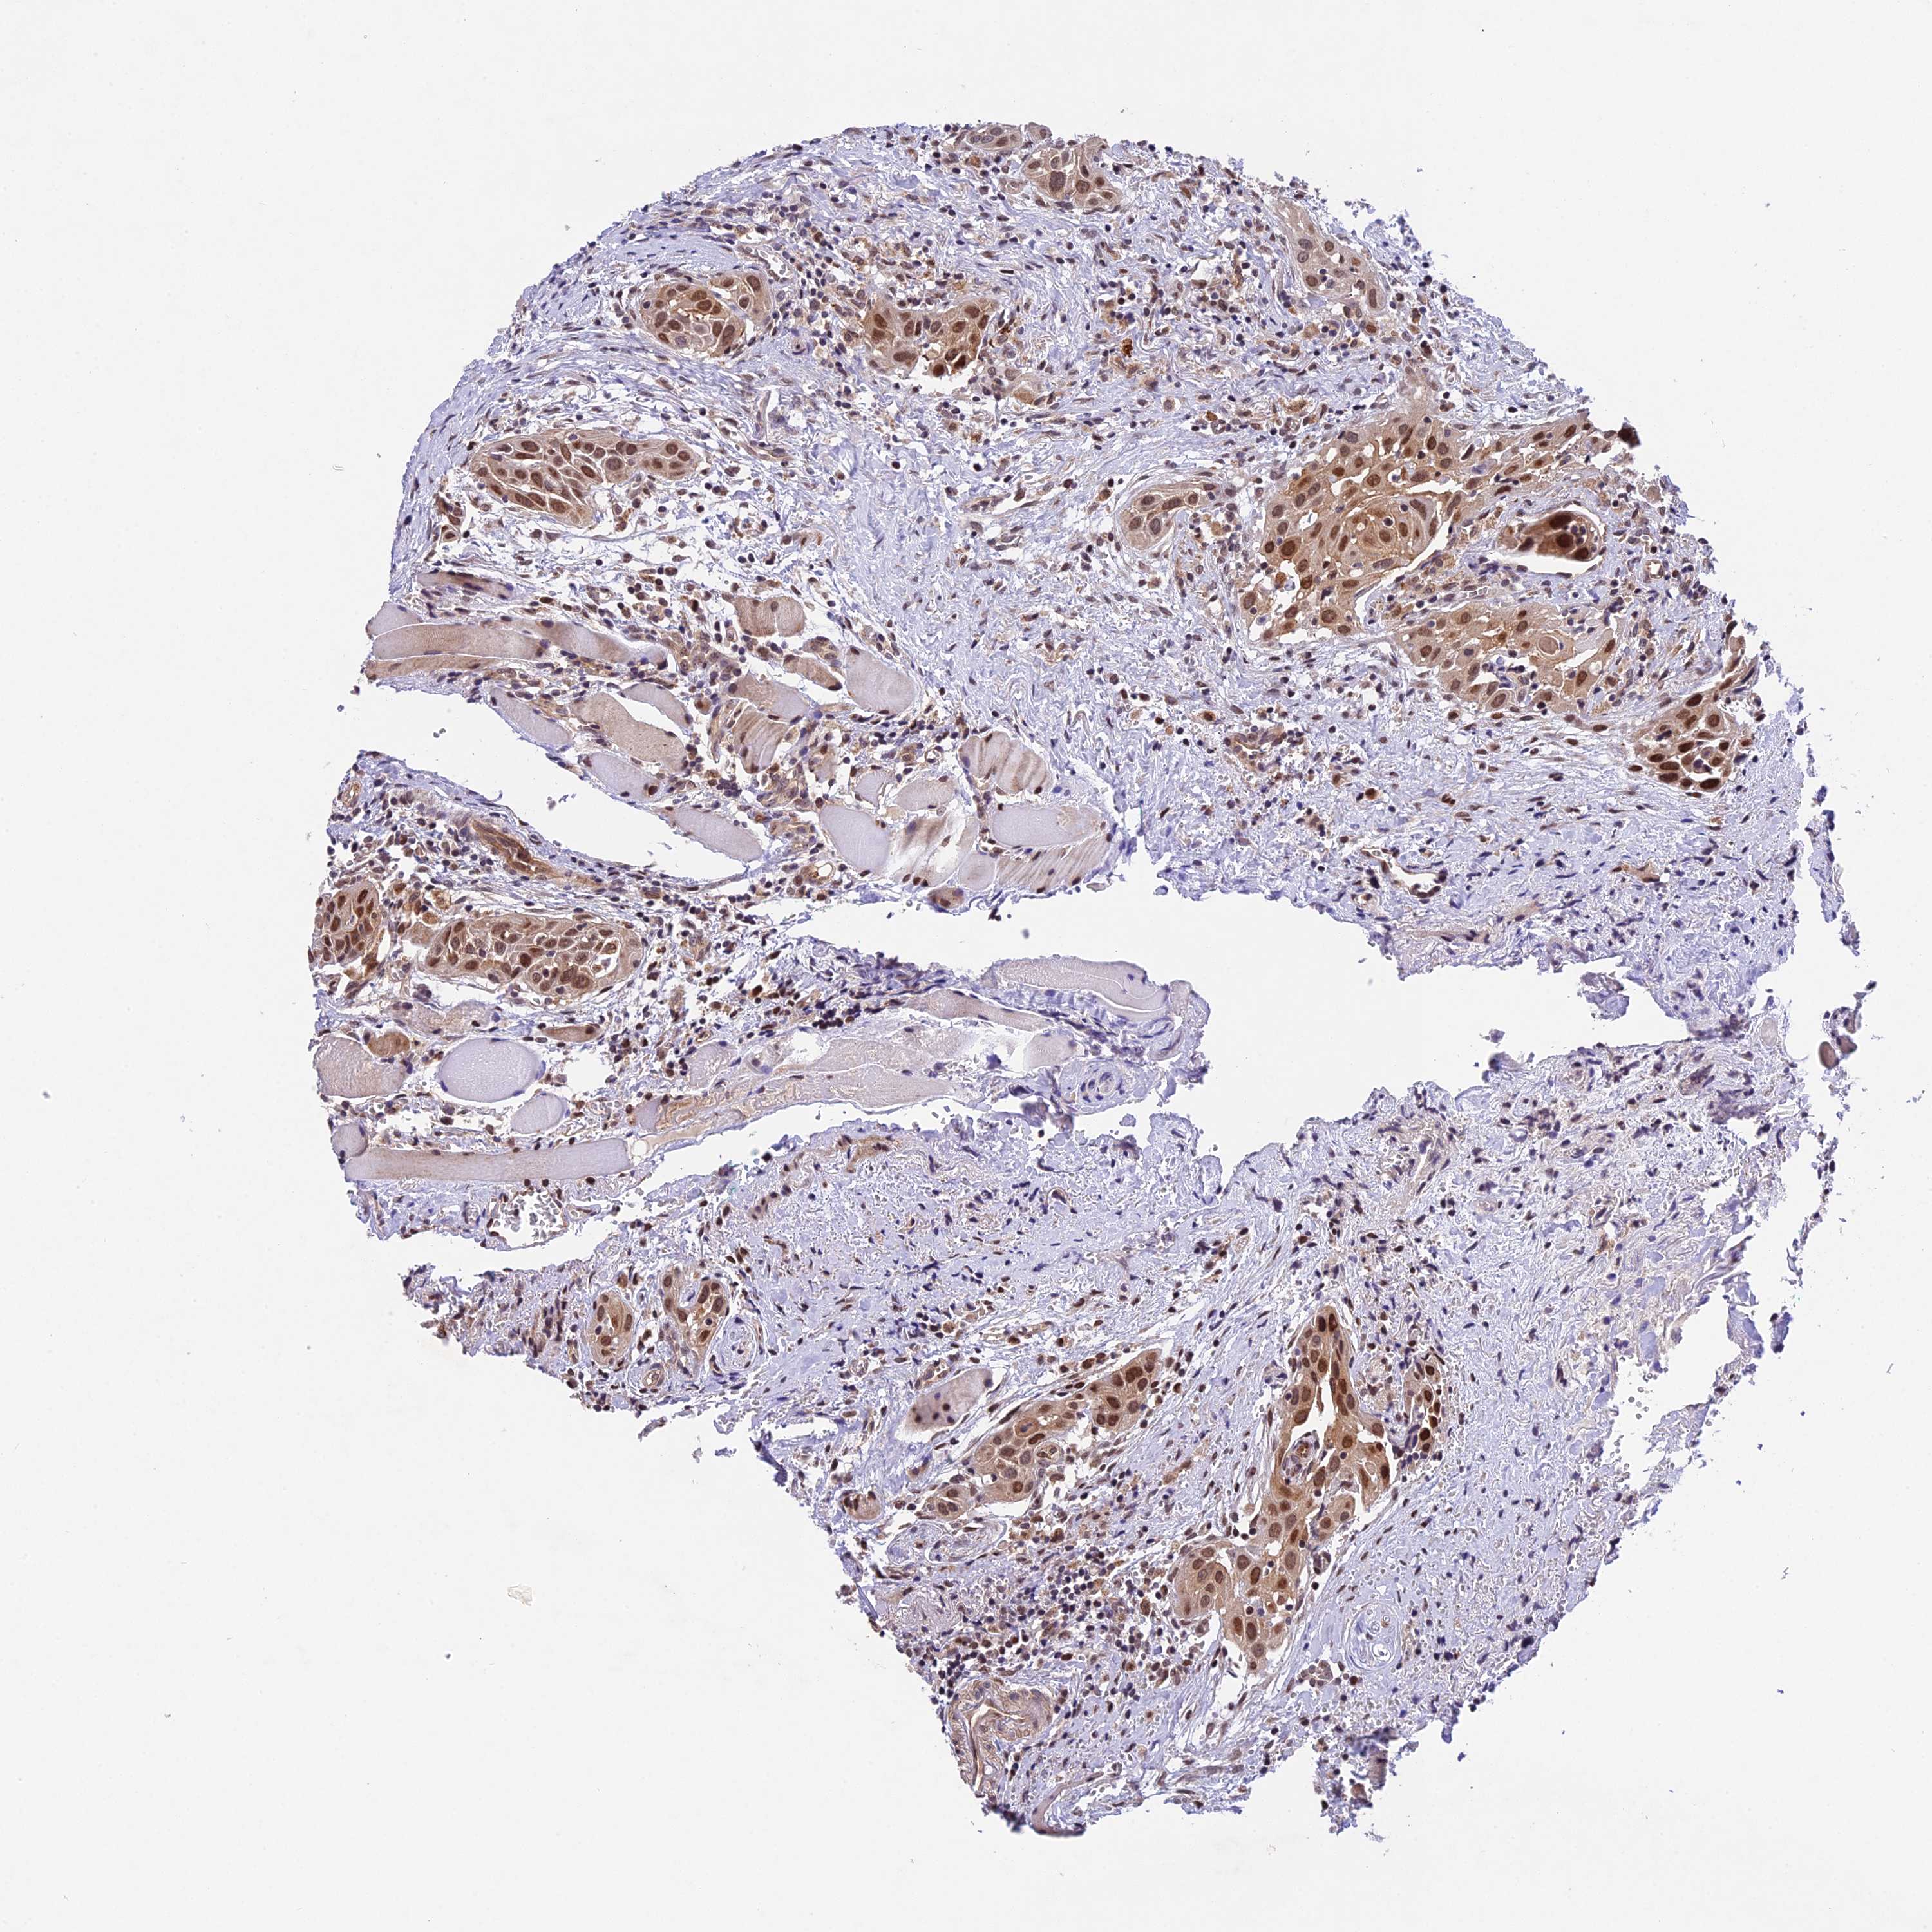

HEAD AND NECK CANCER - Protein expressioni

A mouse-over function shows sample information and annotation data. Click on an image to view it in a full screen mode. Samples can be filtered based on level of antibody staining by selecting one or several of the following categories: high, medium, low and not detected. The assay and annotation is described here.

Antibody stainingi

Antibody staining in the annotated cell types in the current human tissue is reported as not detected, low, medium, or high, based on conventional immunohistochemistry profiling in selected tissues. This score is based on the combination of the staining intensity and fraction of stained cells.

Each image is clickable and will lead to virtual microscopy that enables deeper exploration of all samples and also displays staining intensity scores, fraction scores and subcellular localization as well as patient and tissue information for each sample.

Antibody HPA041880

Antibody HPA054709

Staining

High

Medium

Low

Not detected

Intensity

Strong

Moderate

Weak

Negative

Quantity

>75%

75%-25%

<25%

None

Location

Nuclear

Cytoplasmic/membranous

Cytoplasmic/membranous,nuclear

Squamous cell carcinoma, NOS

Adenocarcinoma, NOS